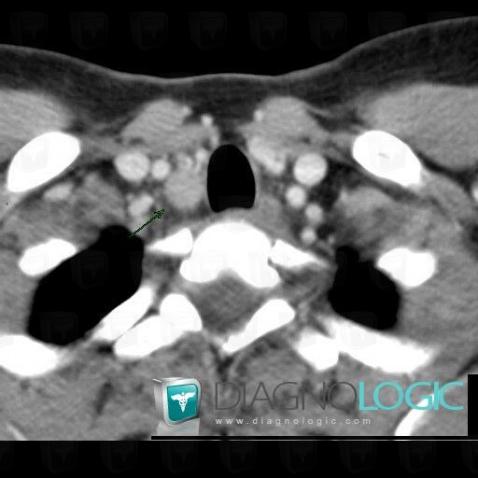

Parathroid adenoma, Thyroid / Parathyroid, CT

Here is the specific information in the key image above:

- Diagnosis Parathroid adenoma, Location(s) Thyroid / Parathyroid, with gamuts